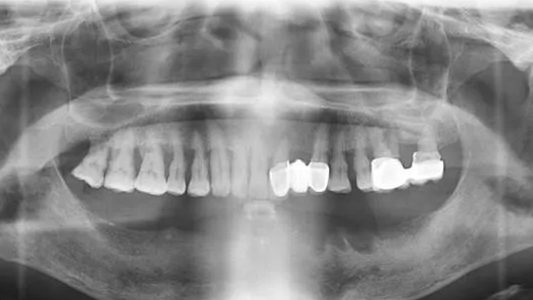

于老伯今年已经65岁了,下半口牙齿寥寥无几,剩下的牙齿也有严重牙周炎,也因为种植牙的费用太高一直也没有进行治疗。近两年,剩下的牙齿晃动更加严重,吃饭都成了一件难事,苹果、西瓜什么更是吃不了,生活质量直线下降,身体健康也受到影响。这才在儿子的劝说下来到圣洁口腔进行治疗。

圣洁口腔姚院长对患者口内情况进行诊断后,表示患者口内情况非常适合ALL-ON-4即刻种植牙,跟患者沟通后,于老伯也对即刻半口种植非常满意。经过医生的术前检查显示于老伯身体一切正常,当天下午就开始了手术,全程手术不到3小时。